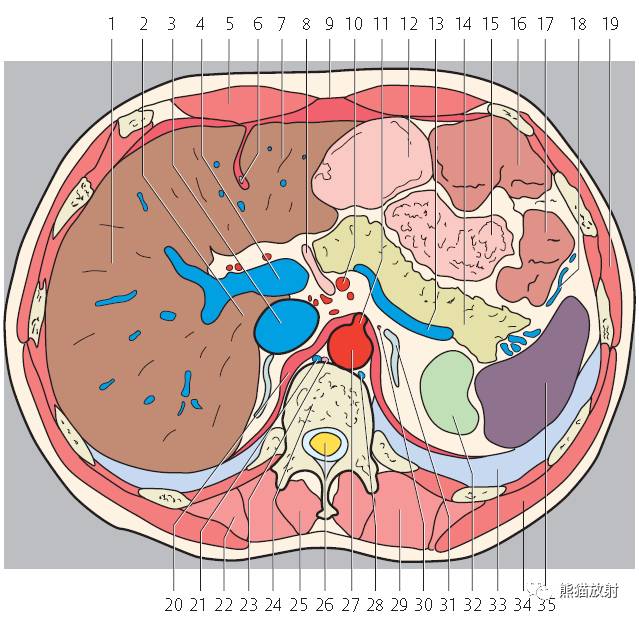

第三层

1、肝右叶;2、肝尾状叶;3、下腔静脉;4、肝门静脉;5、腹直肌;6、肝圆韧带;7、肝左叶;8、十二指肠降段;9、腹白线;10、肠系膜上动脉;11、腹腔干;12、胃;13、脾静脉;14、胰腺;15;空肠;16、横结肠;17、降结肠;18、左结肠静脉;19、腹外斜肌;20、膈肌;21、奇静脉;22、髂肋肌(胸段);23、胸导管;24、胸椎;25、棘肌;26、椎管和脊髓;27、腹主动脉;28、半奇静脉;29、最长肌;30、肾上腺动脉;31、左侧肾上腺;32、左肾;33、左肺;34、背阔肌;35、脾脏;36、肝门区;37、圆韧带凹痕;38、肝十二指肠韧带;39、网膜孔;40、网膜囊/大网膜;41、胰淋巴结;42、右膈下隐窝;43、肝淋巴结;44、腰淋巴结;45、膈上淋巴结;46、后纵隔;47、脾门;48、左结肠旁沟。